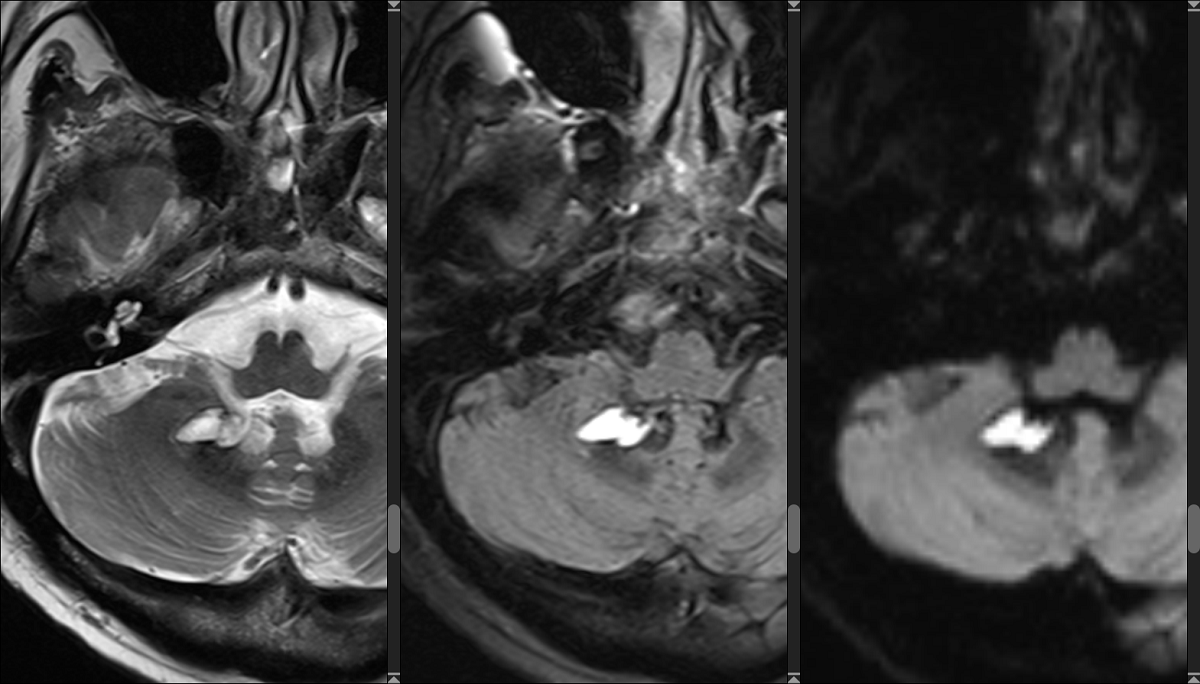

– Базовый курс по МРТ: основы нейрорадиологии;

Для того, чтобы познакомиться с разнообразием методов лучевой диагностики, применяемых для исследования головного мозга и позвоночника мы разработали курс «Лучевая диагностика для неврологов», который научит выбирать наиболее информативный метод диагностики в зависимости от клинической ситуации.